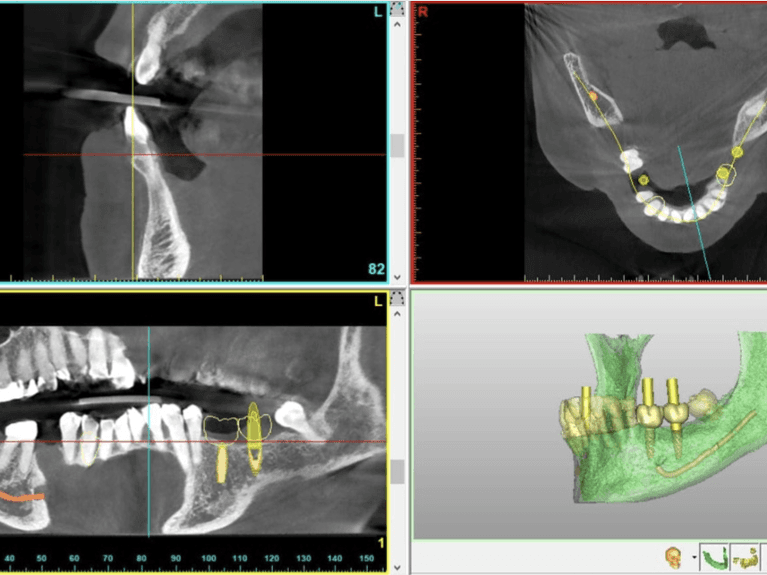

Simplant® Software

This technology is used in the virtual planning for dental implants before they are placed in the jawbone. This technology is designed to improve accuracy and predictability, as well as provide clarity for patients before the procedure.

Orthopos Axeos® - Panoramic X-Rays

Orthophos Axeos® is a 3-D scanner that is designed to deliver efficient patient care without the need to be referred to another place for the scan. We usually use this if we need full mouth x-rays for complex dental problems such as wisdom teeth removal, orthodontics, planning for dental implants or any form of complex dental treatment.